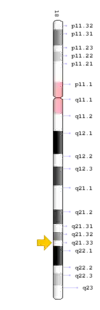

TCIRG1 mutation

The TCIRG1 gene is present in chromosome locus 11q13, which encodes for the a3 subunit of vacuolar H+ ATPase (V-ATPase) that is unique to osteoclasts.[12] The a3 subunit is responsible in anchoring the vacuolar proton pump to the ruffled membrane of osteoclasts.[9] The V-ATPase is important in mediating the transport of hydrogen ions into the resorption lacunae, which is a pit on the bone surface enclosed by the osteoclast for bone resorption. The accumulation of ions in the lacuna facilitates the decomposition of hydroxyapatite crystals by creating an acidic environment, resulting in bone resorption.[12]

TNFRSF11A mutation

The TNFRSF11A gene is present in chromosome locus 18q21.33, which encodes for the receptor activator of NF-κB (RANK).[13] RANK is expressed in immature osteoclasts, which facilitates osteoclasts maturation upon binding of RANK ligand (RANKL). Binding of RANK ligand mediates the RANK/RANKL/OPG signalling pathway. The pathway mediates osteoclast differentiation and activation by promoting differentiation of precursors into multinucleated osteoclasts, and activating osteoclasts, thereby contributing to bone resorption and remodelling. Health conditions related to genetic changes in TNFRSF11A includes osteopetrosis, osteolysis, and Paget's disease of bone.[14][15]

SLC29A3 mutation

The SLC29A3 gene is present in chromosome locus10q22.1, which encodes for the equilibrative nucleoside transporter 3 (ENT3), a nucleoside transporter that is present in membranes of mitochondria and lysosomes.[9] ENT3 is responsible for the trafficking of nucleoside, free purines and pyrimidines into the mitochondria and out of lysosomes.[9][16] Mutations in the gene is often accompanied by histiocytosis-lymphadenopathy plus syndrome, which is characterised by the accumulation of histiocytes leading to lymphadenopathy and other symptoms.[16]